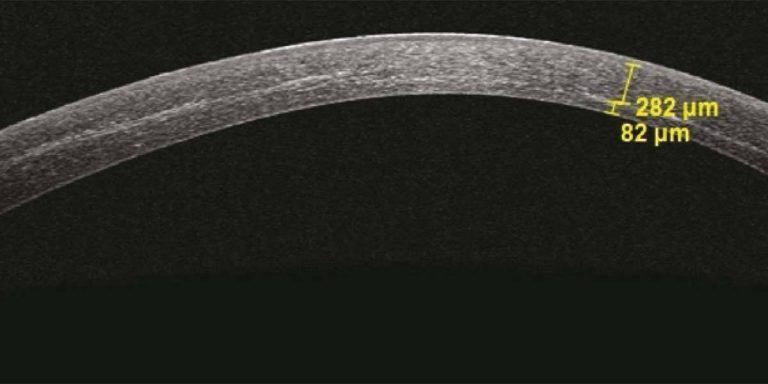

Keratoconus is the progressive thinning of the cornea, and corneal cross-linking (CXL) can successfully treat it.